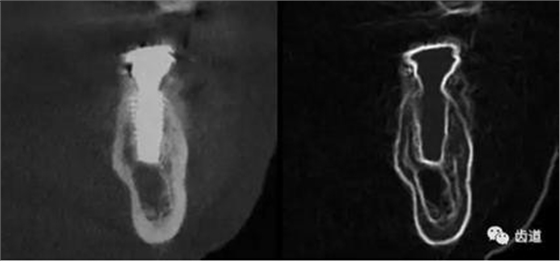

二)牙槽骨外科

CBCT在牙槽骨外科手術(shù)中,通過立體影像可以全面了解牙齒周圍的解剖結(jié)構(gòu),牙根的位置,下頜神經(jīng)管的走向和范圍,上頜竇底的位置及上下牙牙根與上頜竇的關(guān)系,下牙牙根與下頜神經(jīng)管的位置關(guān)系,手術(shù)時(shí)就會“有的放失”,采用更加安全的方法,避免損傷上頜竇和下牙槽神經(jīng)。

1、上頜尖牙阻生

上頜尖牙埋伏阻生在CBCT中的影像